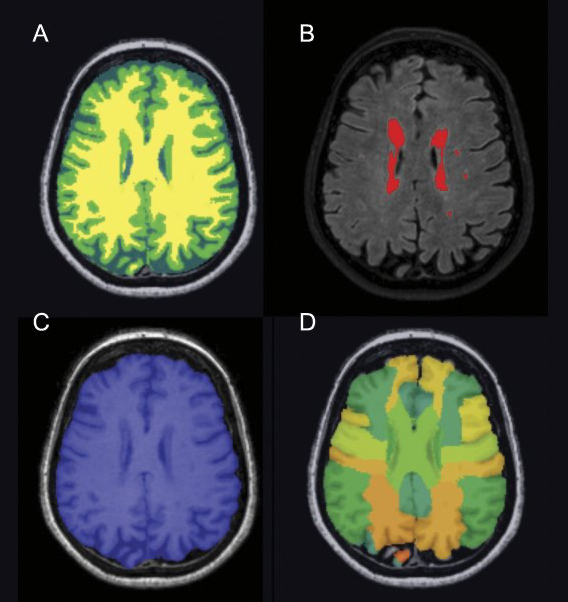

centrale aanpak voor het

invoeren, opslaan en analyseren van de data. Inclusief een geautomatiseerde analyse van MRI-beelden van hart, bloedvaten en hersenen. Delen van deze aanpak, worden inmiddels ook toegepast in andere (CVON) studies.